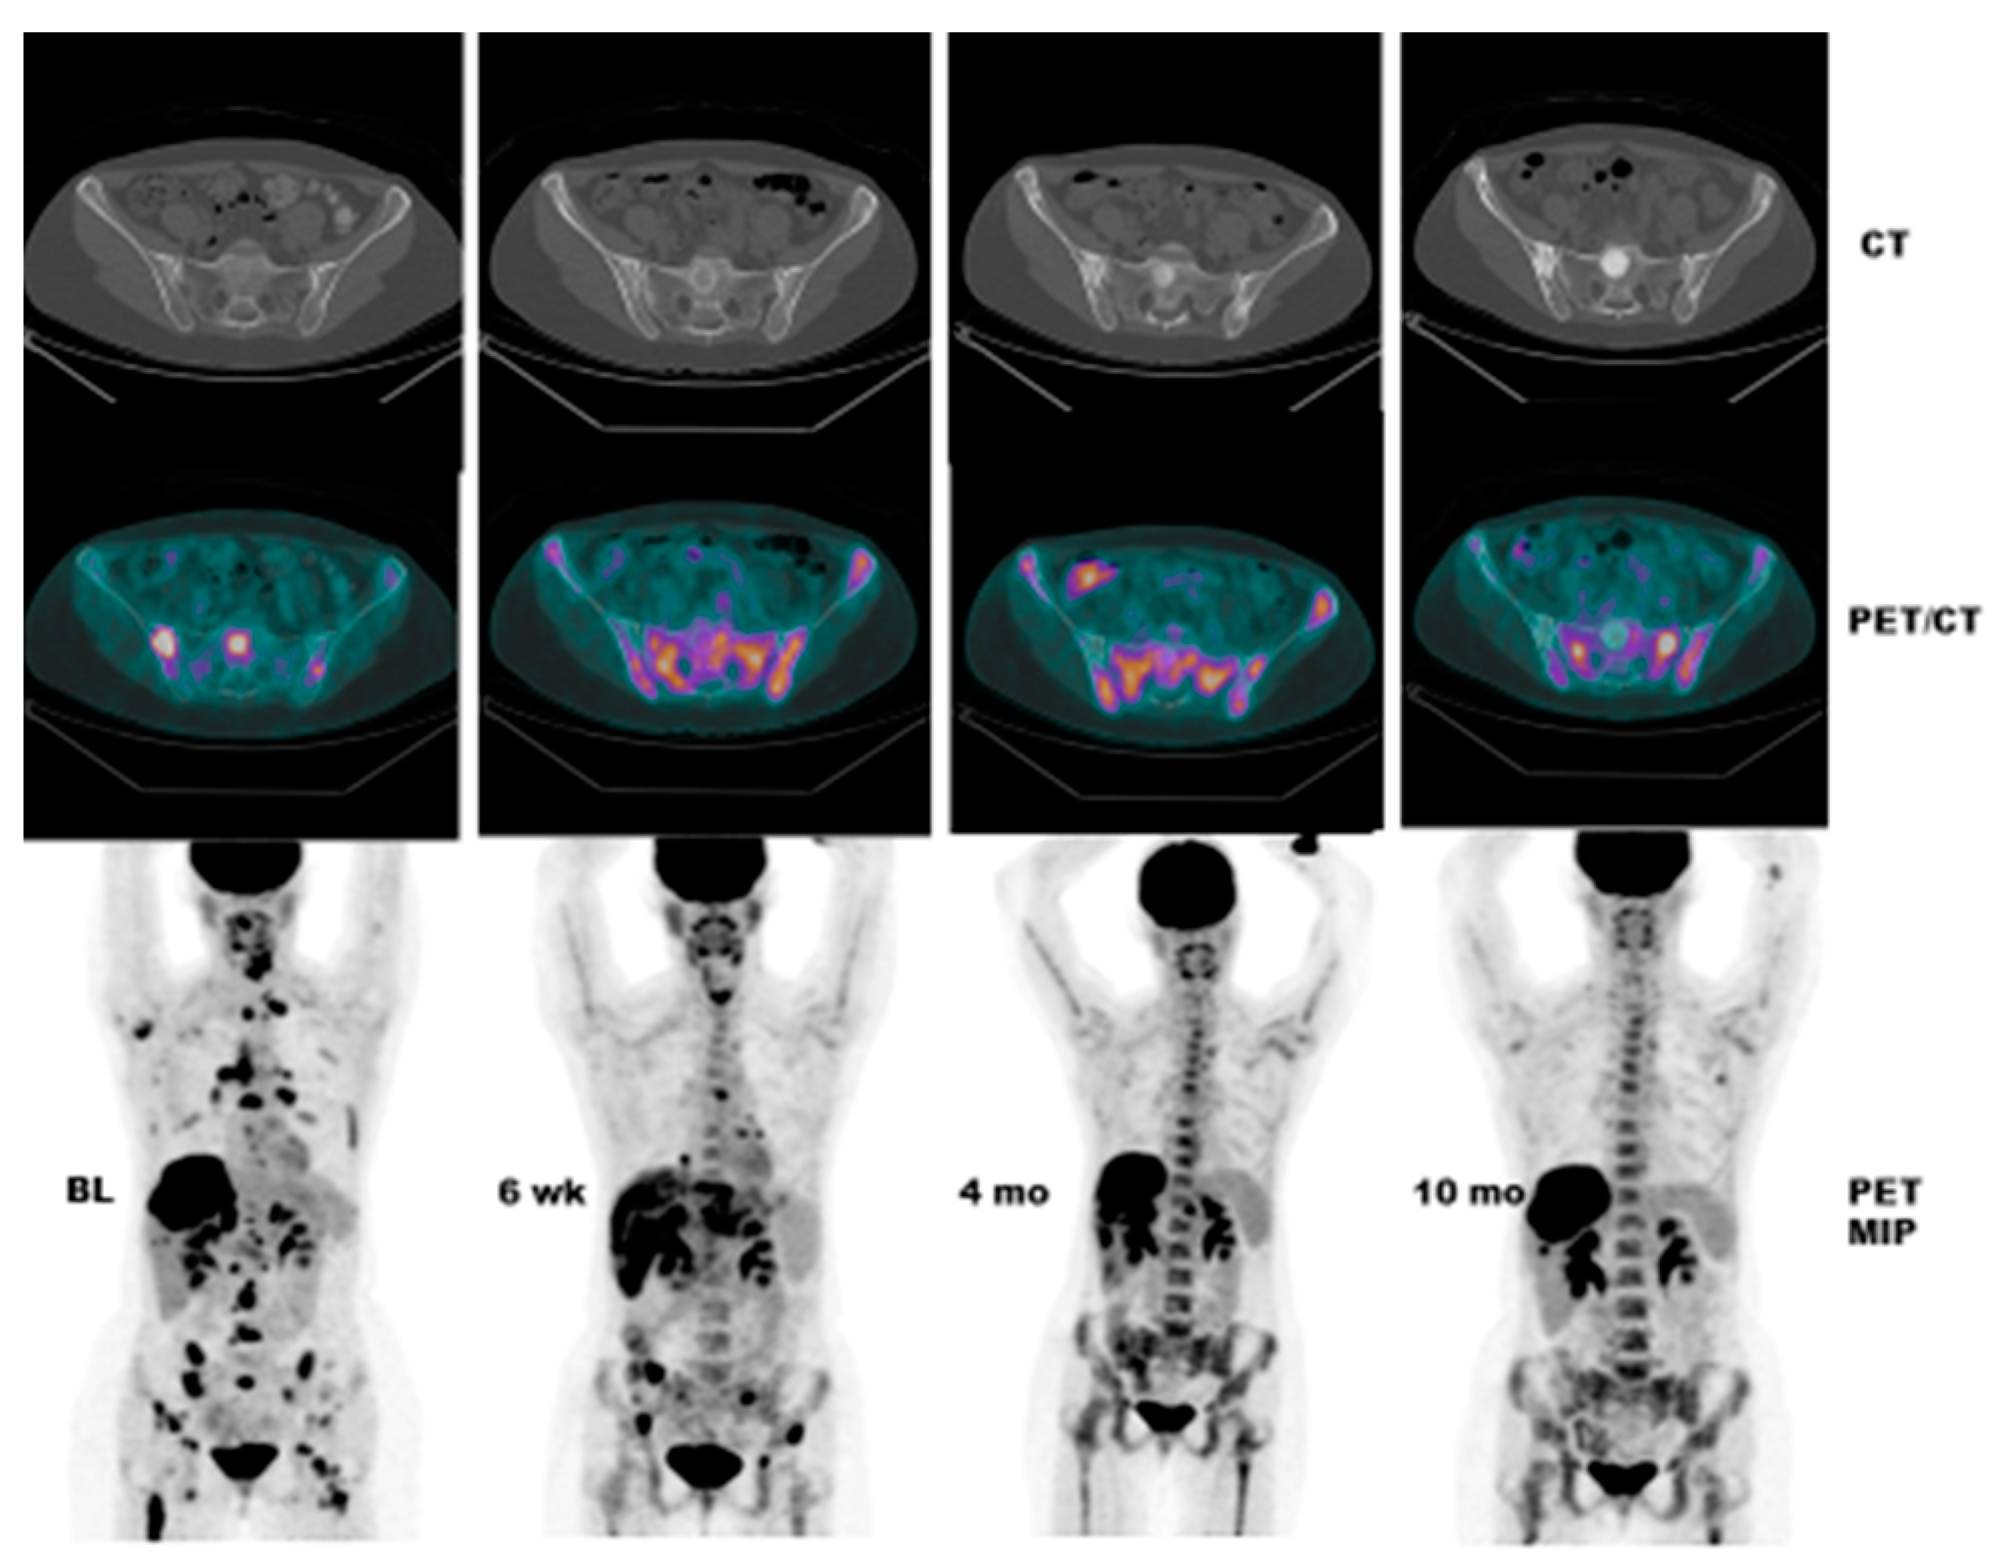

- Case # 1:

- FDG PET/CT was performed in a 47 y/o female with metastatic breast cancer. Patient had multiple osseous metastases. The baseline study showed focal sites of activity in the bone marrow space, without discernible anatomic abnormality (Figure 2). About 6 weeks after starting therapy, there was diffuse marrow activation; however, there was relative loss of normal marrow activity where tumor was previously seen, and there was new sclerotic change at those sites. About 4 months after starting therapy, there was still diffuse marrow activation with loss of normal marrow activity where tumor was, and increased sclerosis on CT images. Unfortunately, about 10 months after starting therapy, she relapsed, with new focal sites of activity, without anatomic abnormality (similar to baseline study), whereas previously tumor sites became densely sclerotic and remained without activity to suggest active tumor.